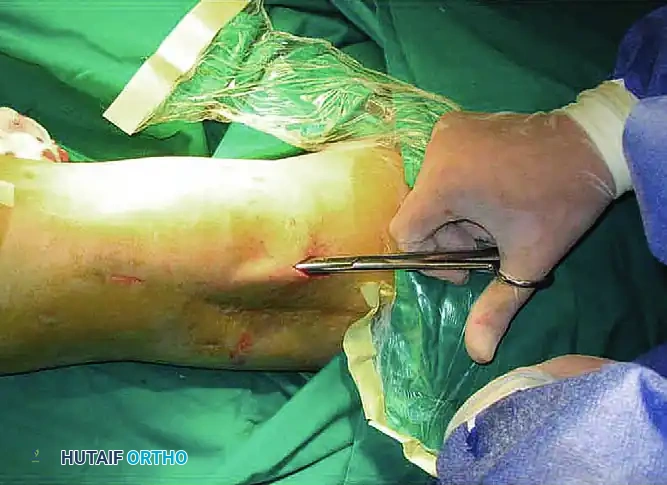

STAGE 1: Lateral Retinacular Release

- Utilizing an inside-out technique, create a percutaneous parapatellar lateral arthrotomy.

- Incise the lateral retinaculum directly from the patella along its lateral border, extending from the superolateral corner of the patella down to the lateral aspect of its lower pole.

- To fully restore the lateral recess, free the lateral retinaculum from the lateral femoral condyle. Continue proximally to free the vastus lateralis tendon and the iliotibial band from their adhesions to the distal third of the femur.